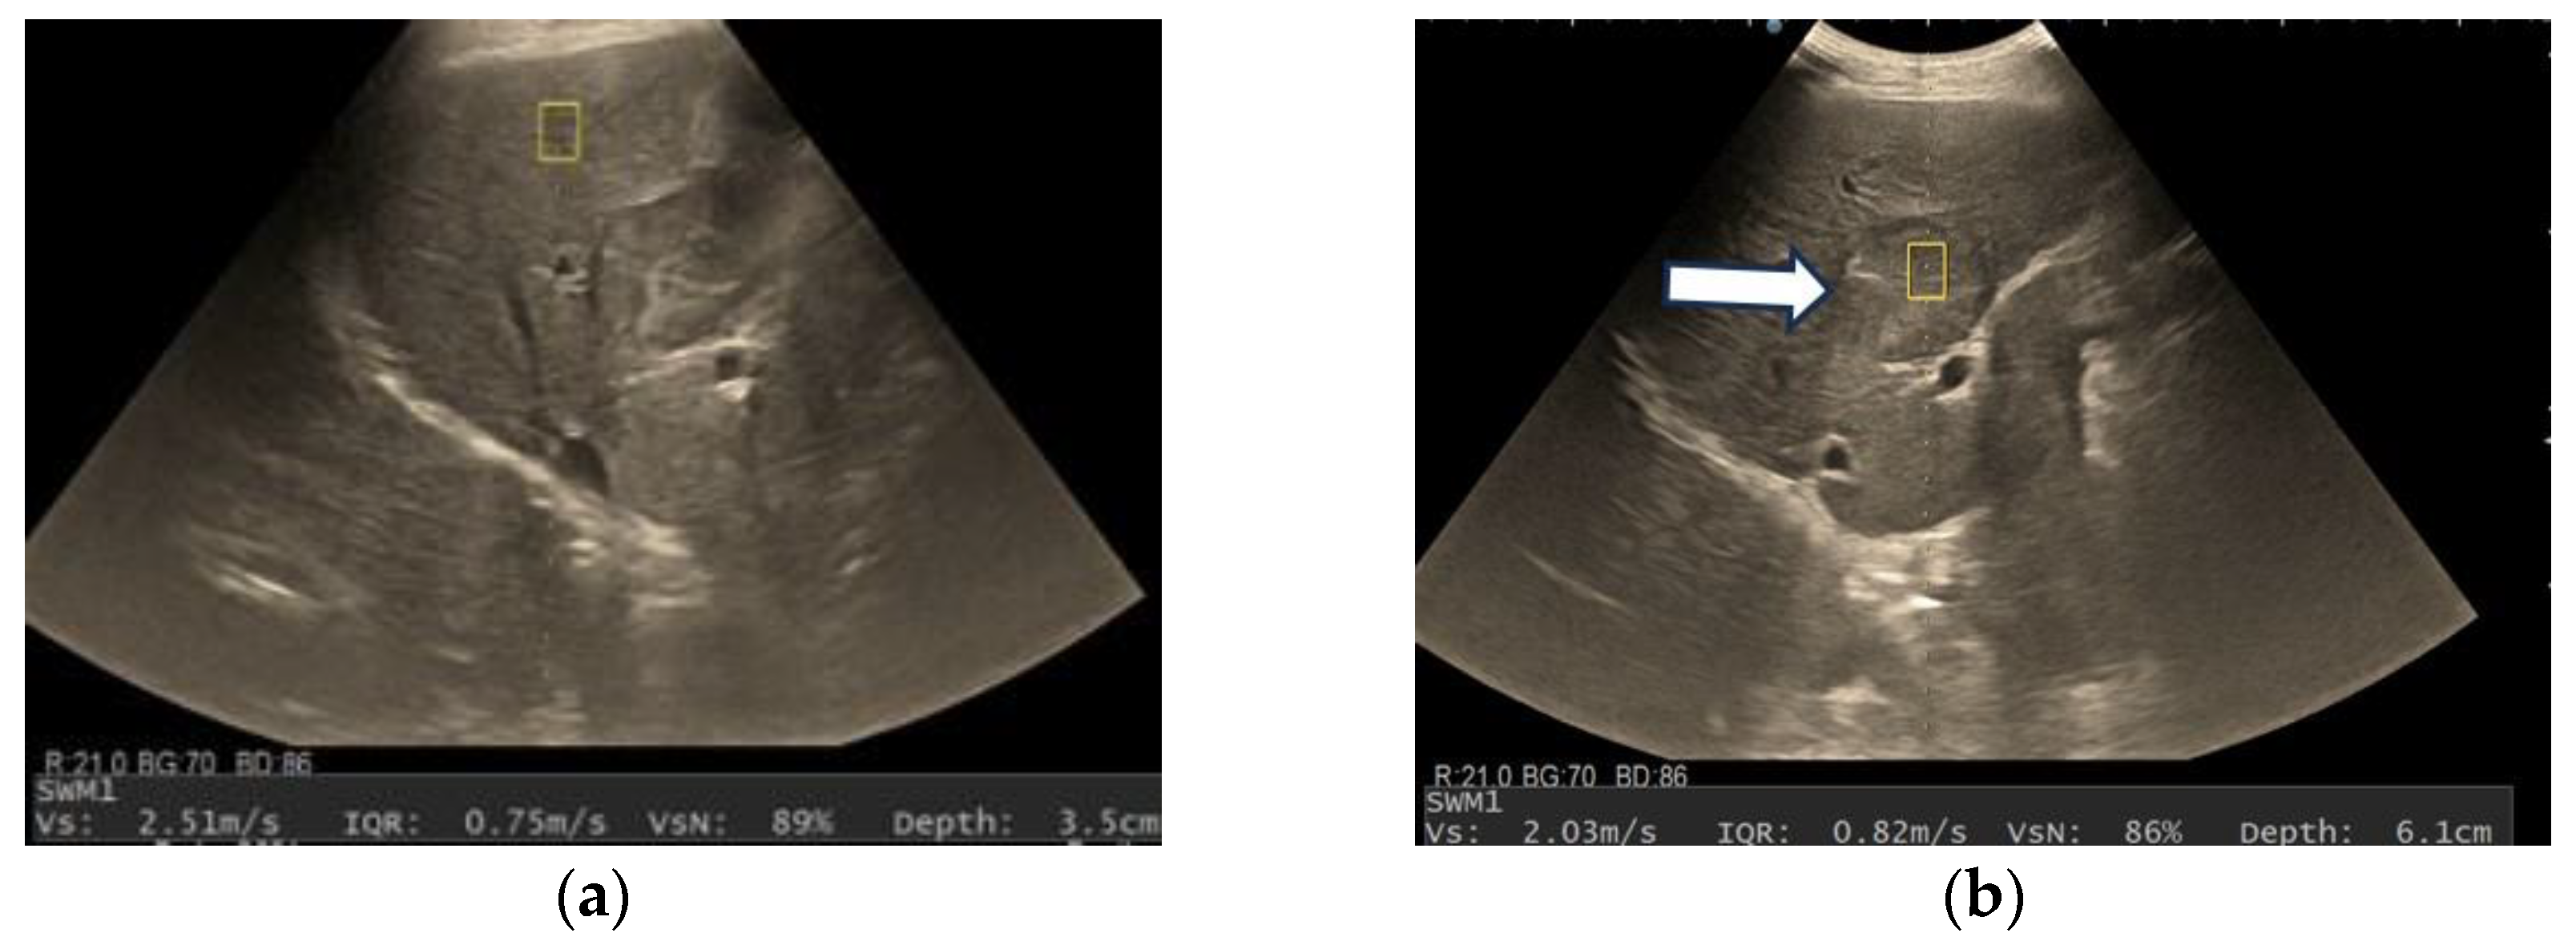

3.3. Shear Wave Measurements in Liver Tumors

| Tumor Type | Mean Vs (m/s) | Range |

|---|---|---|

| HCCs | 1.59 ± 0.29 | 1.07–2.31 m/s |

| Non-HCC malignancies | 1.9 ± 0.42 | 1.34–3 m/s |

| Benign tumors | 1.75 ± 0.4 | 1.36–2.51 m/s |

| Sensitivity (95% CI) | Specificity (95% CI) | PPV (95% CI) | NPV (95% CI) | Accuracy (95% CI) |

|---|---|---|---|---|

| 54.76% | 82.35% | 88.46% | 42.42% | 62.71% |

| (38.67–70.15%) | (56.57–96.20%) | (72.59–95.69%) | (33.09–52.34%) | (49.15–74.96%) |

| Variables | VsN ≥ 50% | VsN < 50% | p-Value |

|---|---|---|---|

| Vs (m/s) | 1.66 ± 0.3 | 1.73 ± 0.44 | 0.74 |

| Depth of the lesion (cm) | 5.14 ± 1.16 | 5.73 ± 1.60 | 1.31 |

| Size (mm) | 75.59 ± 29.62 | 66.17 ± 45 | 0.06 |

| Presence of liver cirrhosis | 17 | 15 | 0.34 |